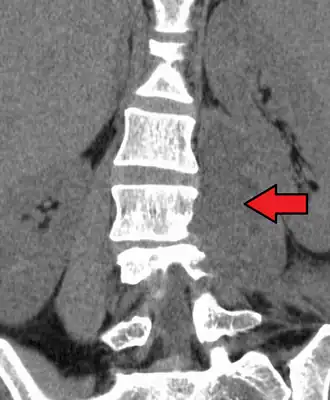

Absceso del psoas

El absceso del psoas es una enfermedad infecciosa que se presenta de manera poco frecuente. Suele ser de diagnóstico tardío, porque se presenta con síntomas inespecíficos.[1]

Los exámenes que se practican, que son el cuadro hemático, la ecografía abdomino-lumbar o la tomografía axial computada, detectan la colección purulenta.